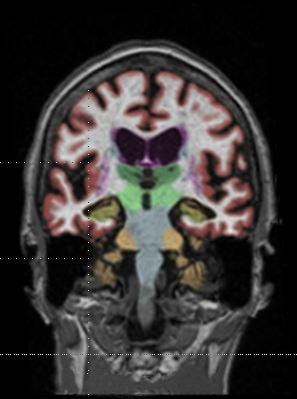

Gadolinium contrast agents (GBCAs) are partly retained in the brain, raising safety concerns, as seen in this MRI.